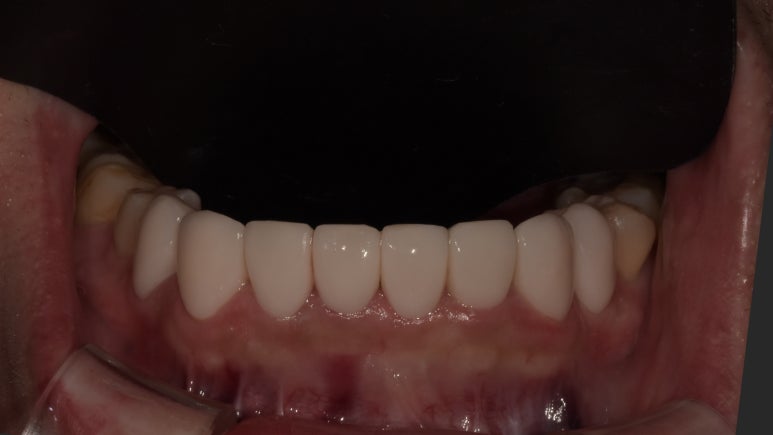

20230411 치료 전

20230422 치료 후

20231107 아랫니 라미네이트 전

20231120 아랫니 라미네이트 후